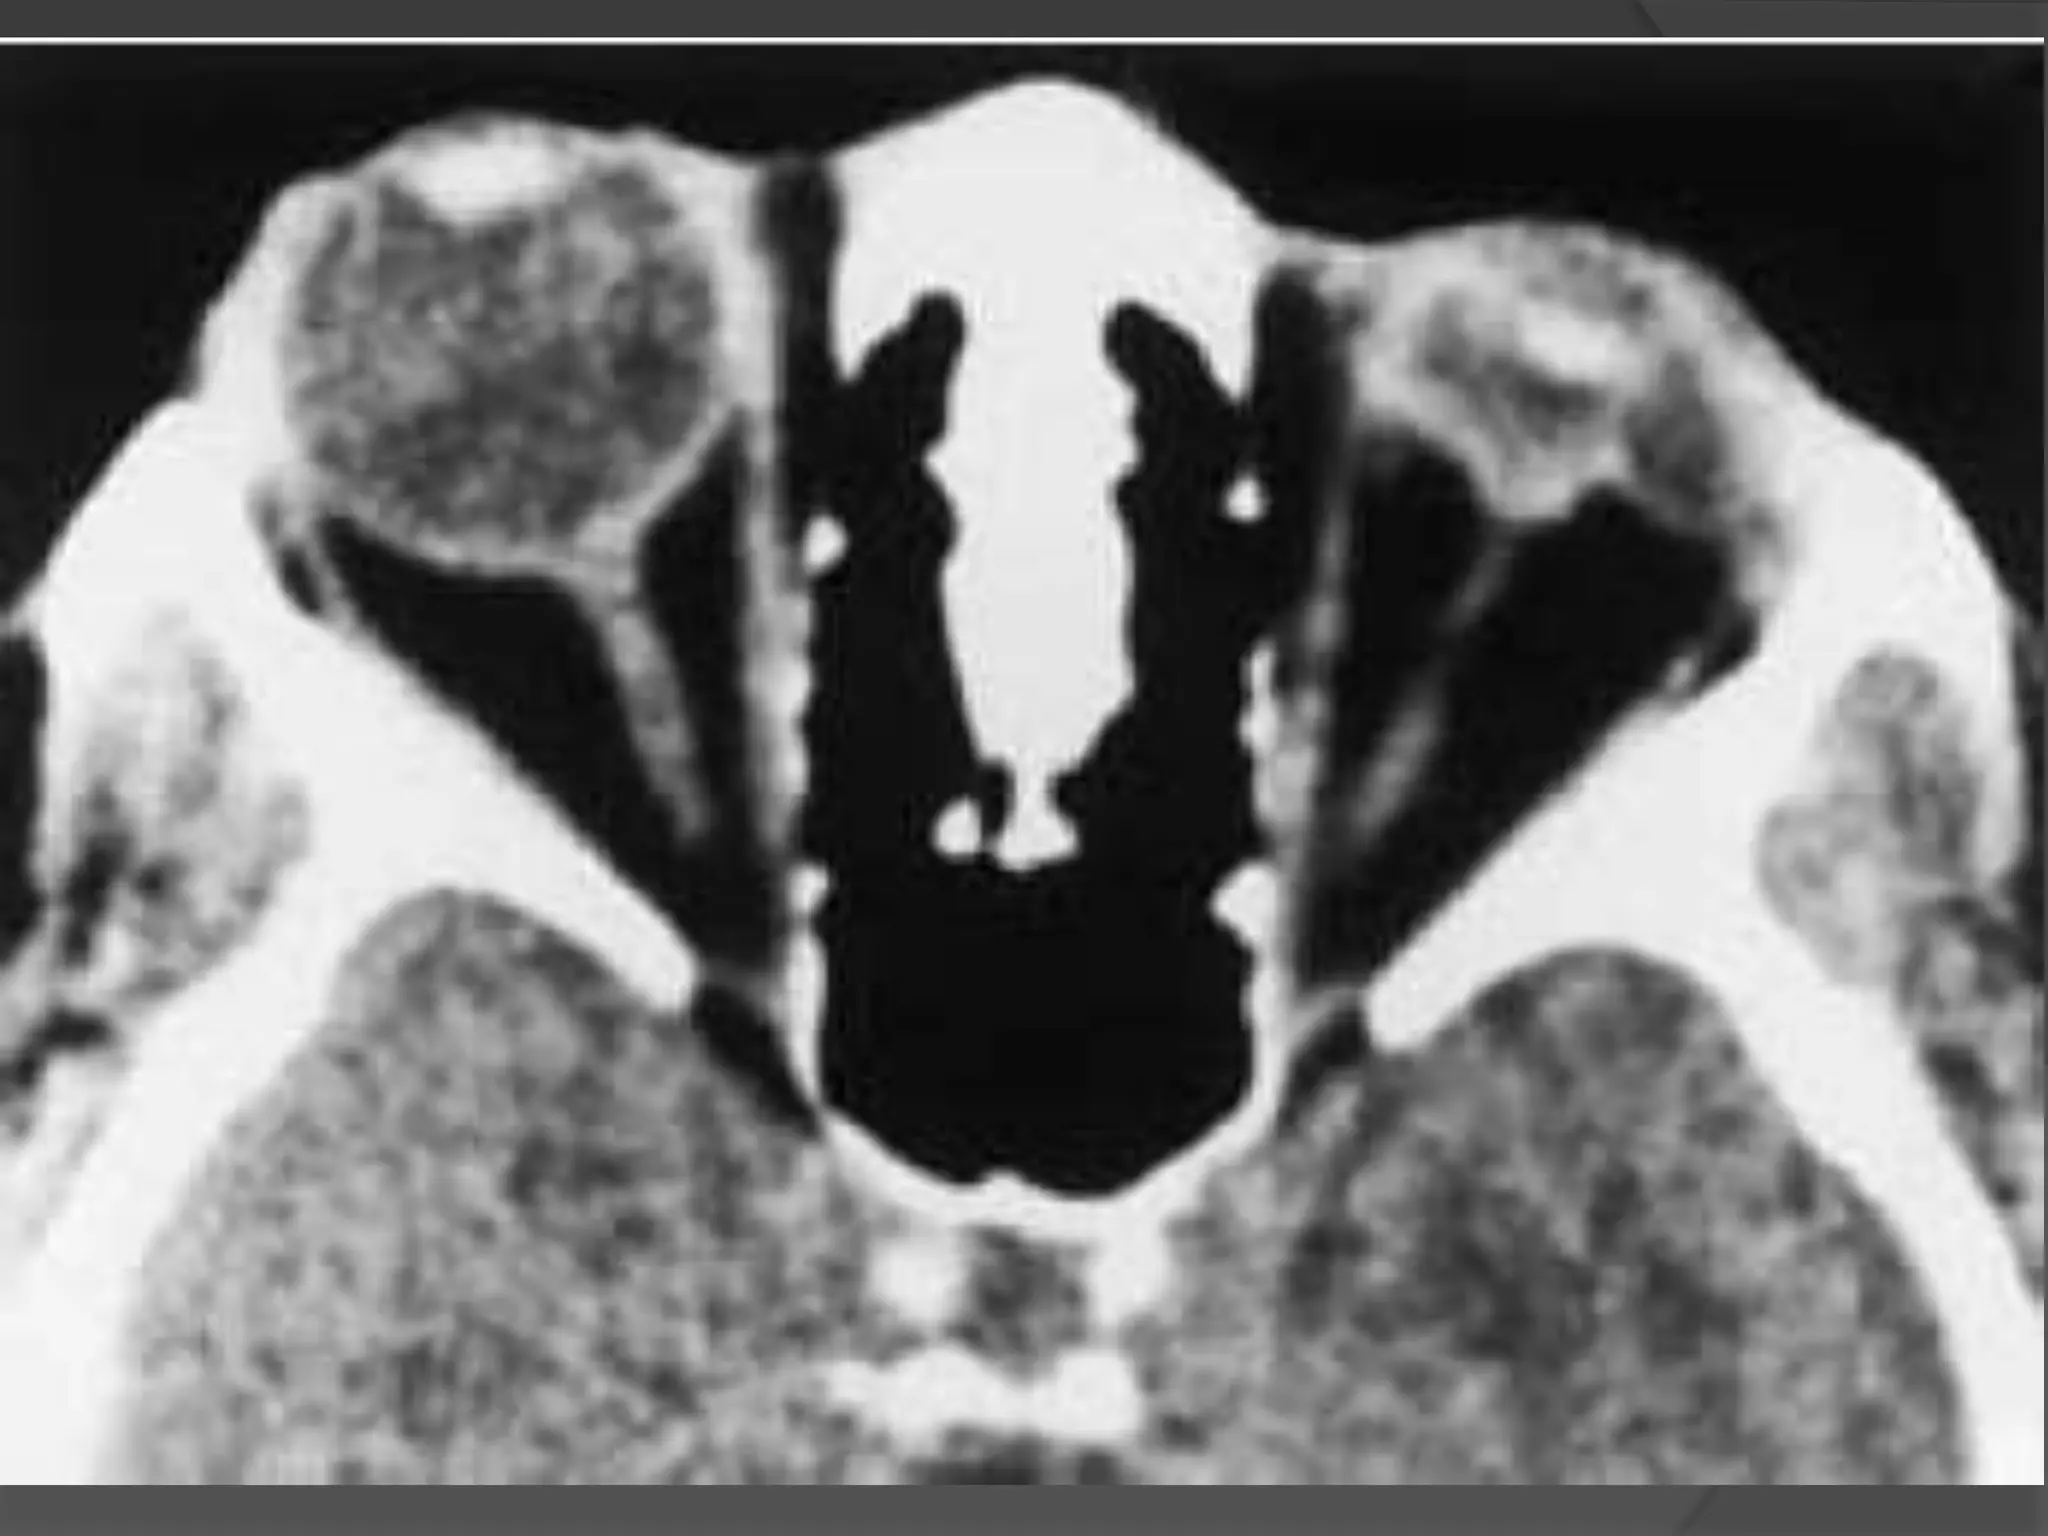

• #77 Scleral buckle in retinal detachment. A to D, Axial CT images showing the linear radial density encircling the globe (arrows). Note that if followed on all images, the radiodensity makes a complete ring around the globe.